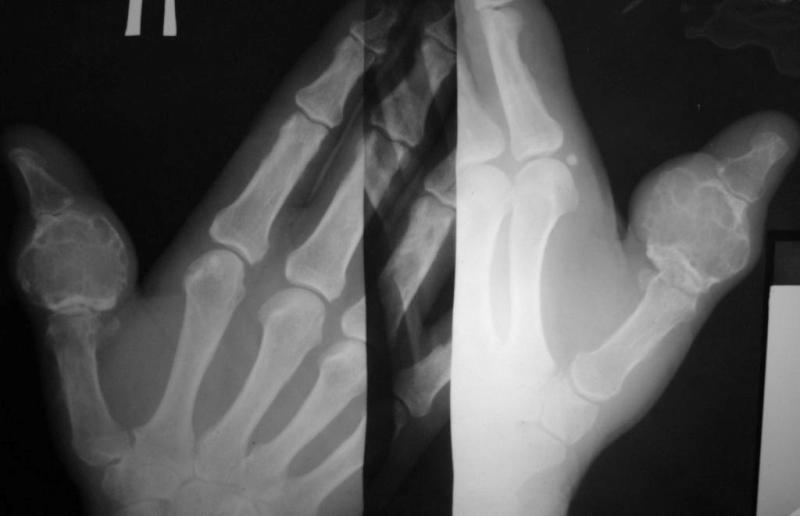

Больная, 68 лет. 10 лет назад со слов больной была травма пальца, за помощью не обращалась, была небольшая припухлость. За последние 2 года отметила рост опухолеподобного образования, появились боли, ограничение движений 1 пальца. При пальпации умеренная болезненость. Наблюдалась в поликлинике по месту жительства с диагнозами - солитарная костная киста, энхондрома.Госпитализирована с диагнозом остеобластокластома проксимальной фаланги 1 пальца правой кисти. Предлагается удаление проксимальной фаланги и костная пластика:1. трансплантатом из гребня подвздошной кости2. трансплантатом из большеберцовой кости3. трансплантатом из головки плюсневой костиУ кого есть какие-то взгляды на лечение даной больной. Спасибо за ответы.

Очень похоже на гигантоклеточную опухоль.

Судя по представленным фотографиям опухолевое образование имеет выраженный мягкотканный компонент, выходит за пределы кортикала фаланги, которая мне видится разрушенной. Даже если это и остеобластокластома (гигантоклеточная опухоль), точно на этот вопрос может ответить лишь морфолог, пластика чем-либо мне видится неадекватным вмешательством, будет рецидив, а рецидивная GCT всегда более "злая", нежели первичная. Я б уже, при такой картине, выполнил бы полный стандарт обследования для больных с впервые выявленной опухолью. Тактика лечения мне видится такой - экзартикуляция на уровне пястно-фалангового сустава, после заключения морфолога - думать далее.

Чрезвычайно похоже на ОБК (красивые "мыльные пузыри")и никак не похоже на энхондрому. Насчет тщательного обследования и обязательной морфологии нет никаких возражений, учитывая возраст больной, наличие очагов просветления и в головке пястной кости, вроде бы и периостальная реакция на пястной кости. Прорыва компактного слоя не видно, что уже хорошо. Если бы это была пястная кость, то в качестве трансплантата можно было бы еще вспомнить и о малоберцовой кости.

Дождемся гистологии, но по операционным снимкам не очень похоже на энхондрому.У нас была подобная картина, гистология показала хондромиксоидную фиброму\ довольно редкая рецидивирующая доброкачественная опухоль\.

Гигантоклеточная опухоль в возрасте 68 лет маловероятна. Сейчас морфологу необходимо изучить материал из разных участков опухоли (высока вероятность озлокачествления). Если диагноз вторичной хондросаркомы подтвердится- тщательное дообследование и наблюдение.

Имеем заключение гистологии - Хондрома